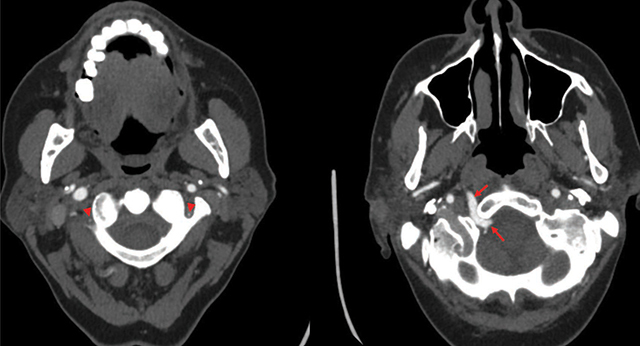

教学要点:持续性舌下动脉是一种极其罕见的解剖变异,但具有诊断和治疗意义。

Teaching point: Persistent hypoglossal artery is an extremely rare anatomical variant but has diagnostic and therapeutic relevance.